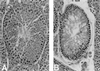

We have generated a mouse model for ataxia-telangiectasia by using gene targeting to generate mice that do not express the Atm protein. Atm-deficient mice are retarded in growth, do not produce mature sperm, and exhibit severe defects in T cell maturation while going on to develop thymomas. Atm-deficient fibroblasts grow poorly in culture and display a high level of double-stranded chromosome breaks. Atm-deficient thymocytes undergo spontaneous apoptosis in vitro significantly more than controls. Atm-deficient mice then exhibit many of the same symptoms found in ataxia-telangiectasia patients and in cells derived from them. Furthermore, we demonstrate that the Atm protein exists as two discrete molecular species, and that loss of one or of both of these can lead to the development of the disease.